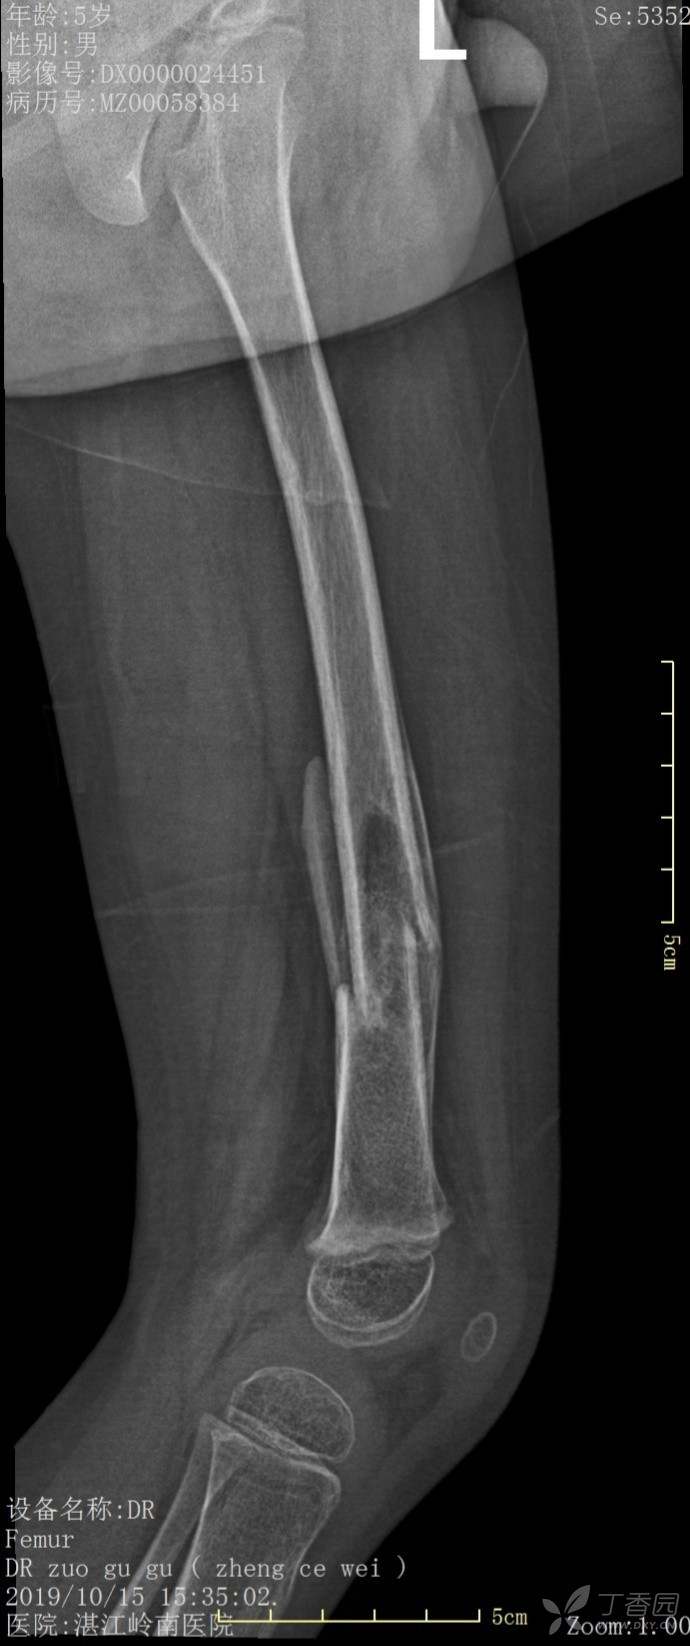

4岁患儿股骨骨折保守治疗一例

外伤时,保守1个月、2个月、6个月